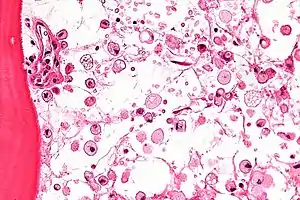

| Micrograph of Gaucher disease, with cells that have the characteristic crumpled tissue paper-like cytoplasm. H&E stain. | |